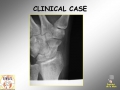

Scaphoid fracture

Scaphoid arthroscopy